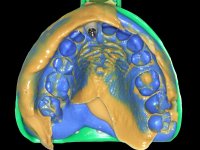

A paciente apresenta um desvio da linha média superior de 6 mm para a esquerda. Resultado da ausência do incisivo central superior esquerdo, os dentes adjacentes inclinaram mesialmente para esta zona, limitando o espaço disponível para a reabilitação prostodontica. Existe uma significativa desarmonia dentária negativa no arco maxilar como resultado da ausência do 21, ausência do primeiro pre-molar com um espaço residual, significativa redução coronária do segundo pre-molar direito, migração dos dentes posteriores para os espaços não preenchidos e uma mesialização molar superior esquerda e direita com uma relação molar em Classe II. Ambos os caninos esquerdo e direito mostram uma relação Classe II na posição de inter-cuspidação máxima. A paciente apresenta uma linha de sorriso média, um biótipo gengival médio grosso, apresenta uma correcta higiene oral sem doença periodontal. Não apresenta hábitos para –funcionais. O exame radiográfico mostra uma significativa inclinação dos eixos dos dentes 11 e 22 com espaço entre a porção apical das raízes. A análise cefalométrica foi feita com o intuito de explorar a hipótese de conseguir arranjar espaço para a colocação de um implante e de uma coroa no local do dente 21. Finalmente a morfologia do osso residual presente na região anterior da maxila foi avaliado com uma TAC, revelando uma perda das dimensões da parede óssea vestibular.

3) Colocação de um implante no espaço criado na zona do 21 associada a uma regeneração óssea guiada da zona,